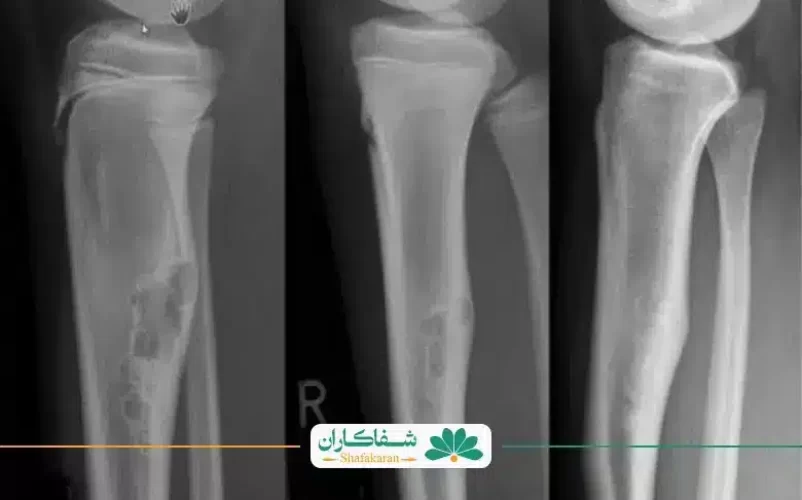

استئوسارکوم شایعترین نوع سرطان استـخوان به حساب میآید که در بین مردان شایعتر است. این بیماری بیشتر در کودکان و نوجوانان زیر ۲۰ سال رخ میدهد. جمعیت بالای ۶۰ سالهها نیز ۱۰% از افراد مبتلا به این بیماری را به خود اختصاص میدهند. علائم سرطان استخوان از نوع استئوسارکوم به طور معمول در استخوانهای اطراف زانو، مانند استخوان ساق پا یا پایین ران ایجاد میشود.

جراحی برای درمان سرطان استخوان در زانو برای حذف یا جایگزینی بخشهای آسیب دیده استخوانی صورت میگیرد. در برخی مواقع شدید، ممکن است برای درمان بیمار مجبور به قطع عضو و حذف استخوان آن شوند.